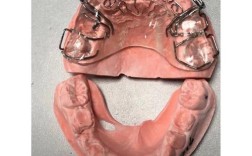

正畸指簧是口腔正畸治疗中常用的一种机械性矫治装置,主要应用于可摘矫治器或固定矫治器的辅助部件,通过金属丝的弹性变形产生持续、轻柔的矫治力,以引导牙齿向目标位置移动,作为正畸治疗中精细调整牙齿位置的重要工具,指簧的设计和应用需严格遵循生物力学...